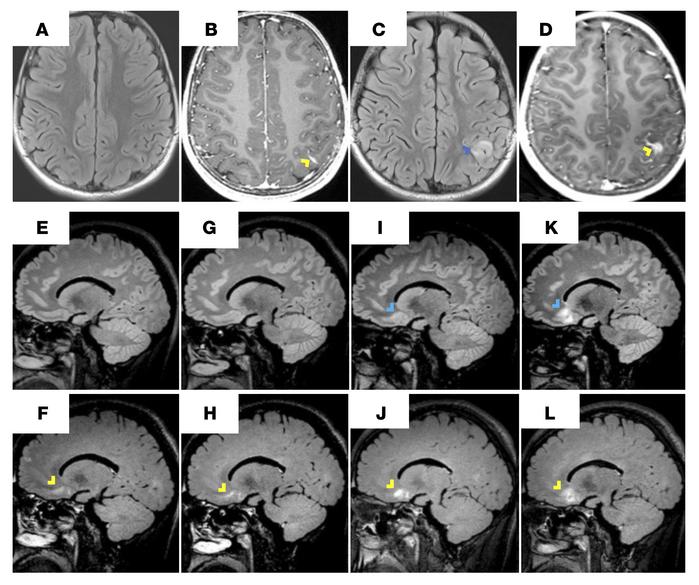

CTLA4h-associated neuroinflammation often starts in the leptomeninges.

LME on MRI can precede parenchymal lesion formation. Patient numbers given here correspond to the data in Table 2. (A–D) Patient 9 developed headaches and a complex partial seizure attributed to a mesial temporal lobe lesion (not shown). MRI scans at clinical onset (A and B) and 11 days later (C and D) show a fast temporal evolution of LME (yellow chevron) to a parenchymal lesion (blue chevron). T2-FLAIR images (A and C); T1-weighted images after contrast (B and D). (E–L) Patient 13 was clinically asymptomatic and had extensive LME (yellow chevrons) on sequential MRIs, each done approximately 1 month apart. T2-FLAIR images (E, G, I, and K); T2-FLAIR images after contrast (F, H, J, and L).